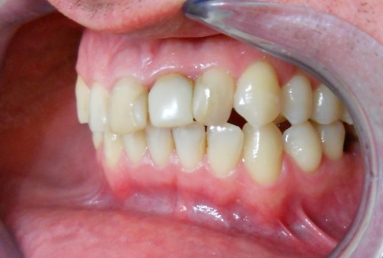

The orthodontic treatment was necessary as the upper maxillary developed assimetricaly, also the teeth were malpositioned. The purpose of the partial braces was to help the final prosthetic treatment, which consisted of two full ceramic crowns for the central incisors, that had root canal treatments, and a ceramic veneer for the lateral incisor, that had a large composite filling. Gingivectomies were also necessary for the right canine and incisors in order to correct the assymetrical gummy smile.